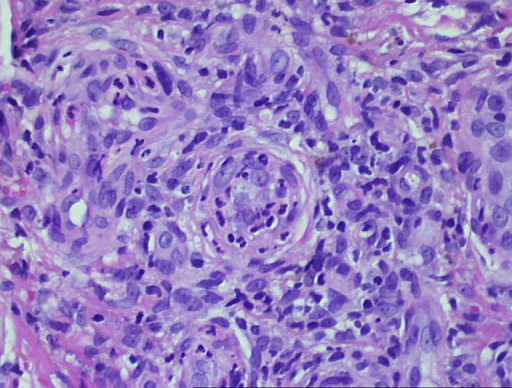

Da die beteiligten Granulozyten beim Durchwandern der Gefäßwände selbst zugrunde gehen, bezeichnet man diese Erkrankung auch als leukozytoklastische Vaskulitis (Abb. 3).

Abb. 3: Histologischer Befund einer leukozytoklastischen Vaskulitis in der Übersicht, die Epidermis ist partiell zerstört und abgehoben, es besteht ein massives zelluläres Infiltrat der Dermis (a). In den Gefäßen und den Gefäßwänden finden sich segmentkernige Granulozyten. Fibrinoide Nekrose der Gefäßwände und zerfallende Granulozyten, die auch perivaskulär abgelagert sind (b,c). Residuale Obstruktion und Infarzierung kleiner kutaner Blutgefäße (d,e).